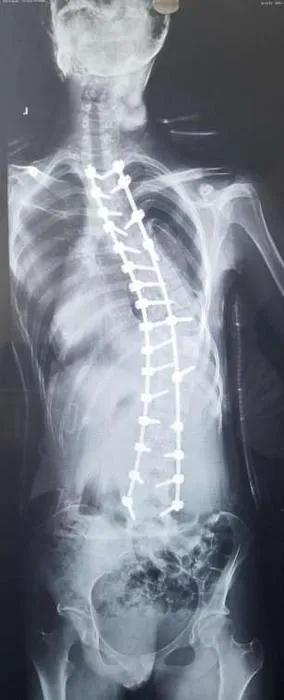

矫形前影像学图。(受访者供图)

矫形后影像学图。(受访者供图)

“经过完善的术前检查与准备,入院后的第三天我们给小雅进行了脊柱侧弯后路截骨矫正术”,手术用时三个半小时”马原主任说,先采用薄层CT扫描,获得小雅的脊柱数据之后,再通过3D打印机打印出与人体椎体1:1的脊柱模型,最终通过术前设计好的置钉点和角度固定成模板导管,对患者的脊柱进行匹配,从而实现精准置钉的目的。

由于小雅的侧弯角度比较大,达到了85,又处在青春发育时期,若是侧弯角度进一步加重,就可能会影响到心肺等功能,因此,当务之急需要接受矫形手术。

马原说,脊柱侧弯患者的脊椎旋转、变形,传统手术置钉完全要依靠手术医生的临床经验,稍有偏差就有可能损伤到神经。在精准医疗的理念下,决定3D打印技术辅助进行脊柱侧弯矫形手术。